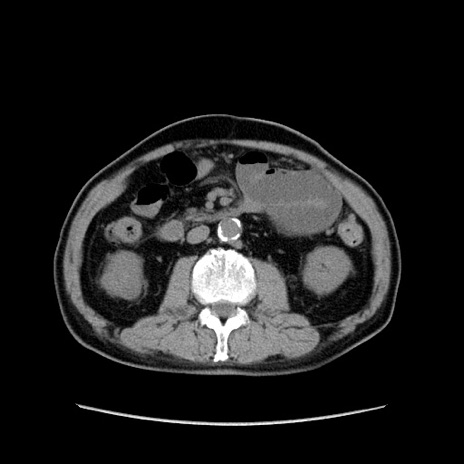

症例24(横断像)

【症例】80歳代男性

【主訴】左側腹部痛、嘔吐

【現病歴】本日早朝より左腹部に痛みあり。昼頃嘔吐認めたため、救急要請。

【既往歴】直腸癌(Mile手術)、胆摘

【身体所見】意識清明、BT 35.9℃、BP 221/93mmHg、SpO2 97%(RA) 、腹部:左ストーマ周囲に限局性の腹部膨隆あり。 膨隆部自発痛・圧痛あり・軟。

【データ】WBC 7700、CRP 0.09